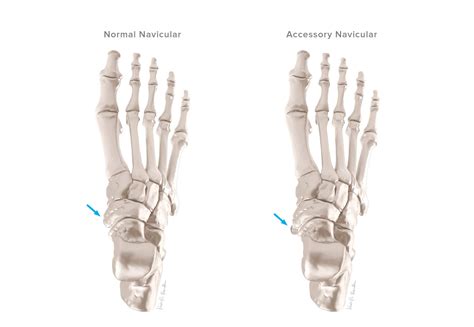

The human foot is a complex structure composed of numerous bones, muscles, and ligaments, each playing a crucial role in supporting the body's weight and facilitating movement. Among the various bones in the foot, the accessory navicular bone is a lesser-known but significant component that can sometimes cause discomfort and require medical attention. This bone is an extra bone or accessory bone that is located on the inner side of the foot, near the navicular bone. Understanding the accessory navicular bone, its causes, symptoms, and treatment options is essential for anyone experiencing foot pain or discomfort.

The accessory navicular bone is a congenital anomaly, meaning it is present at birth. It is an extra bone or a prominence of the navicular bone, located on the inner side of the foot, just above the arch. This bone is connected to the navicular bone by a fibrous or cartilaginous structure. The accessory navicular bone is relatively common, with estimates suggesting that it affects about 4% to 21% of the population. However, not everyone with an accessory navicular bone experiences symptoms.

• Imaging Tests: X-rays, MRI, or CT scans may be ordered to visualize the accessory navicular bone and assess its structure and connection to the navicular bone.

These diagnostic tools help determine the type of accessory navicular bone and the extent of any associated symptoms.